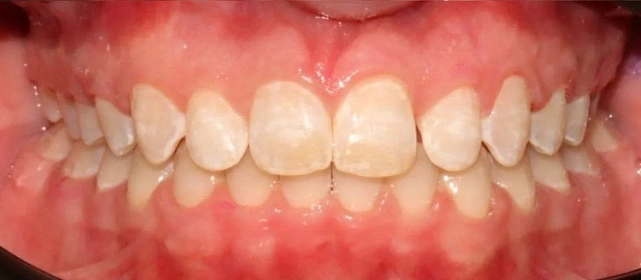

Нарушение соотношения челюстей и неправильное положение зубов — зубные ряды смыкались некорректно, зубы стояли со смещением.

Проблема: Пациентку беспокоило неправильное смыкание зубов и их положение — ряды не сходились как нужно, зубы стояли со смещением. Это влияло и на внешний вид, и на то, как распределялась нагрузка при жевании.